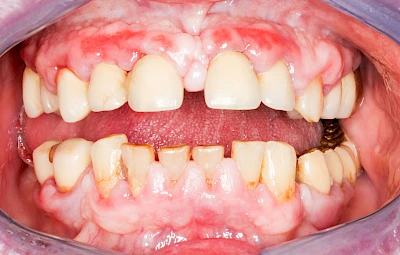

Bakterien in den Zahnbelägen greifen neben den Zähnen auch das Zahnfleisch (Gingiva) und den gesamten Zahnhalteapparat (Parodont) an. Der Körper reagiert mit einer Entzündung, sichtbar als Rötung und Schwellung. Meist blutet das Zahnfleisch z .B. beim Essen oder auch beim Putzen der Zähne.

Ist zunächst nur das Zahnfleisch von der Entzündung betroffen, spricht man von Gingivitis. Später, wenn auch der Knochen um die Zähne herum entzündet ist, spricht man von einer Parodontitis. Bei der Parodontitis wird der Knochen nach und nach abgebaut und das Zahnfleisch zieht sich zurück. Die Zahnhälse und Zahnwurzeloberflächen liegen mehr und mehr frei. Die Zähne werden zunehmend lockerer und fallen schließlich aus.